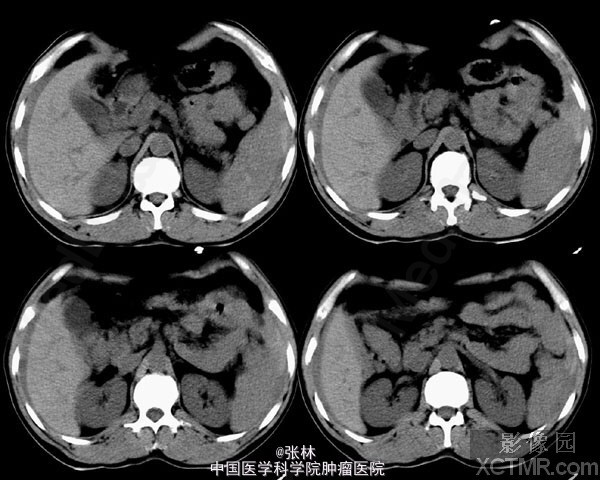

【病史临床】患者,男性,44岁,上腹外伤,疼痛伴呕吐2小时之主诉来诊。CT表现:肝脏周围积液征象,脾脏形态不规则,脾周可见略高密度影。 结果:手术记录如下:(剖腹探查)取上腹正中切口,探查见腹盆腔有较多的积血和血凝块,脾脏表面凹凸不平,肝、脾周有积血。收除腹盆腔积血约1000ML。仔细探查于脾上极脏面可见一深约2cm,长约4cm裂口,时有出血。 最后诊断:外伤性脾破裂。